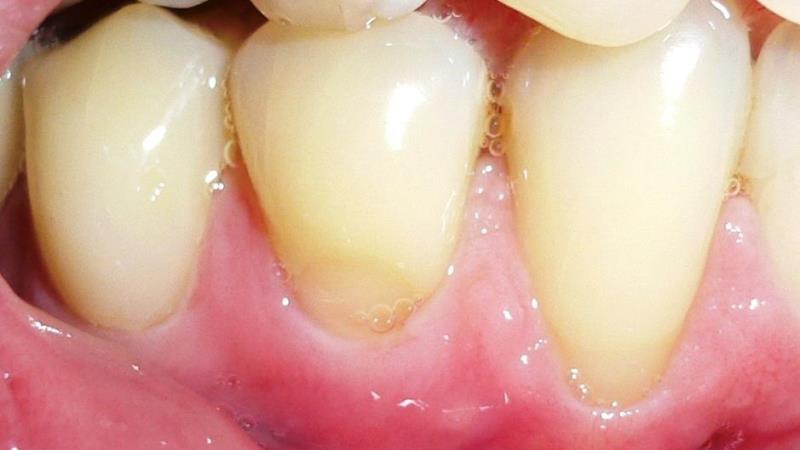

Что касается симптомов, то на начальной стадии заболевание практически не заметно визуально или проявляется слабо. Пациенты могут ощущать повышенную чувствительность эмали к температурным и вкусовым раздражителям, а также к механическим воздействиям (например, жесткая щетка, кусание ручки или употребление твердой пищи).

С течением времени в области шейки зуба появляются неглубокие щели, которые постепенно принимают клиновидную форму. Обычно эти щели располагаются симметрично на зубах одной челюсти, в то время как случаи единичных поражений встречаются крайне редко.

- Стоматологические проблемы. Опущение или поднятие десны может привести к обнажению чувствительной шейки зуба, что создает условия для образования микроскопических трещин.